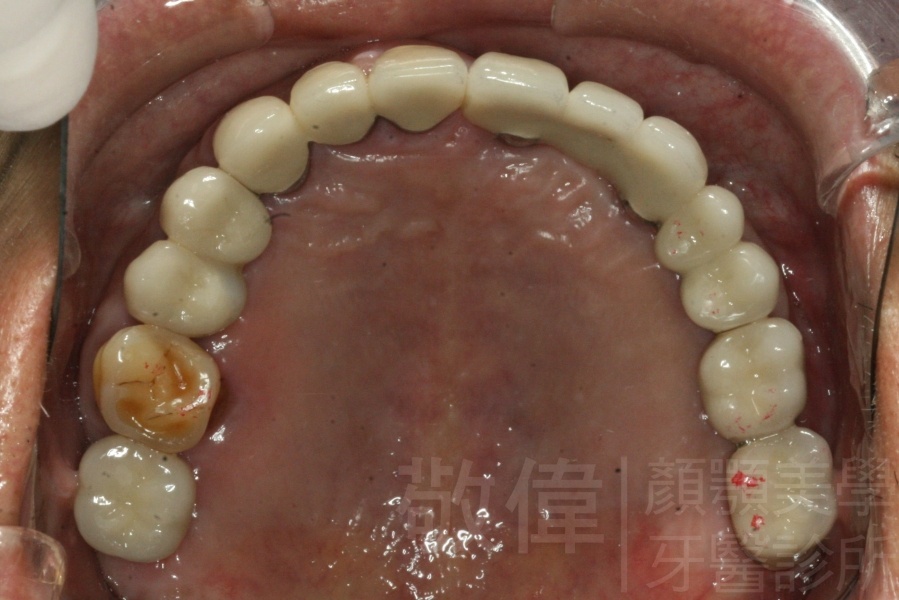

治療前上顎   治療前正面   治療前下顎

治療後上顎   治療後正面   治療後下顎